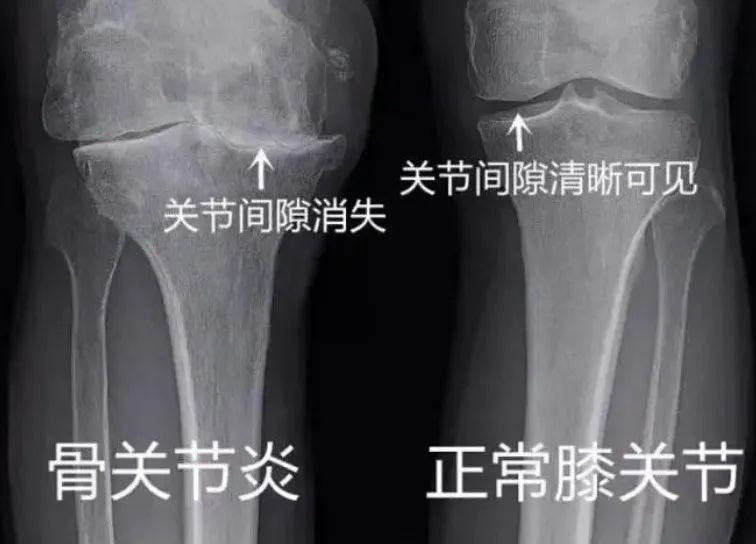

看看两张膝关节照片有何不同?